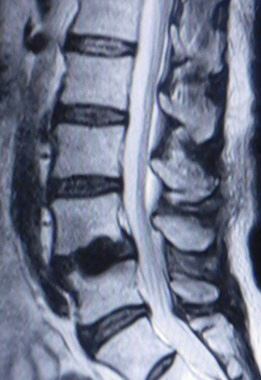

ヘルニコア

腰椎には椎体と椎体の間にクッションの働きをしている椎間板という組織があります。 椎間板は加齢とともにそのクッション性が失われることがあります。椎間板のすぐそばには脊柱管という神経組織が存在する通路があります。椎間板ヘルニアは傷んだ椎間板が脊柱管の方に出っ張ってしまい、神経に当たってしまい炎症を起こし腰痛や下肢痛を起こしてしまう病気です。 腰椎椎間板ヘルニアの治療には飲むお薬、神経根ブロック、手術治療というものが一般的でした。そこに2018年から「ヘルニコア」というコンドリアーゼを有効成分とする腰椎椎間板ヘルニアに対する薬剤が認可されました。椎間板内酵素注入療法という治療方法で呼ばれ、ヘルニコアは椎間板内に注入することにより椎間板の内圧が下がりヘルニアによる神経への圧迫が軽減することにより症状を改善させることが期待されます。 局所麻酔で行います。X線透視で部位を確認しながらヘルニアを生じている椎間板に細い針を刺し、ヘルニコアを注入します。治療に要する時間は約5分程度です。当院では1泊2日で行っております。 椎間板内酵素注入療法(ヘルニコア)はすべての腰椎椎間板ヘルニアに対して適用されるわけではありません。また、人生で一度きりの方法になります。外来で担当医師にご相談ください。